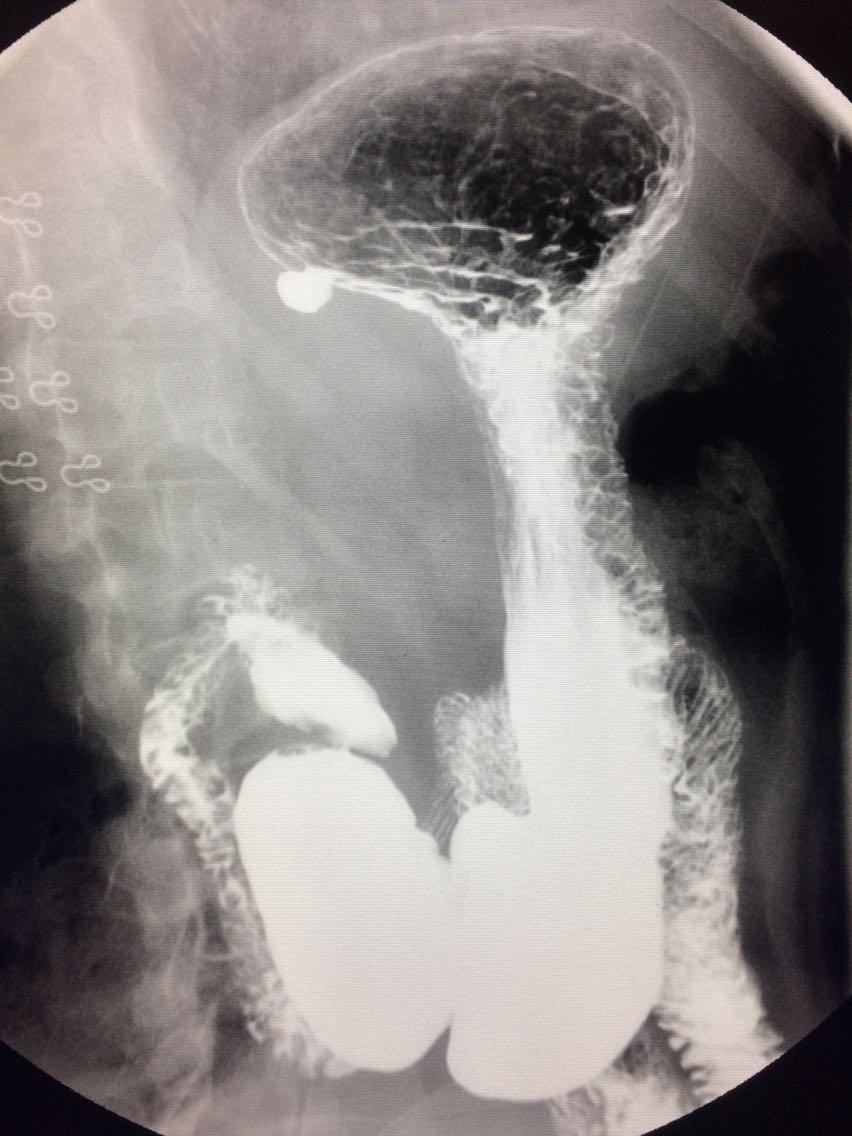

胃底憩室一例

女.47岁 体检来诊。 平素体健,无明显症状。 做上消化道造影如图。

诊断,胃底憩室。 治疗,患者无明显症状,未予治疗。